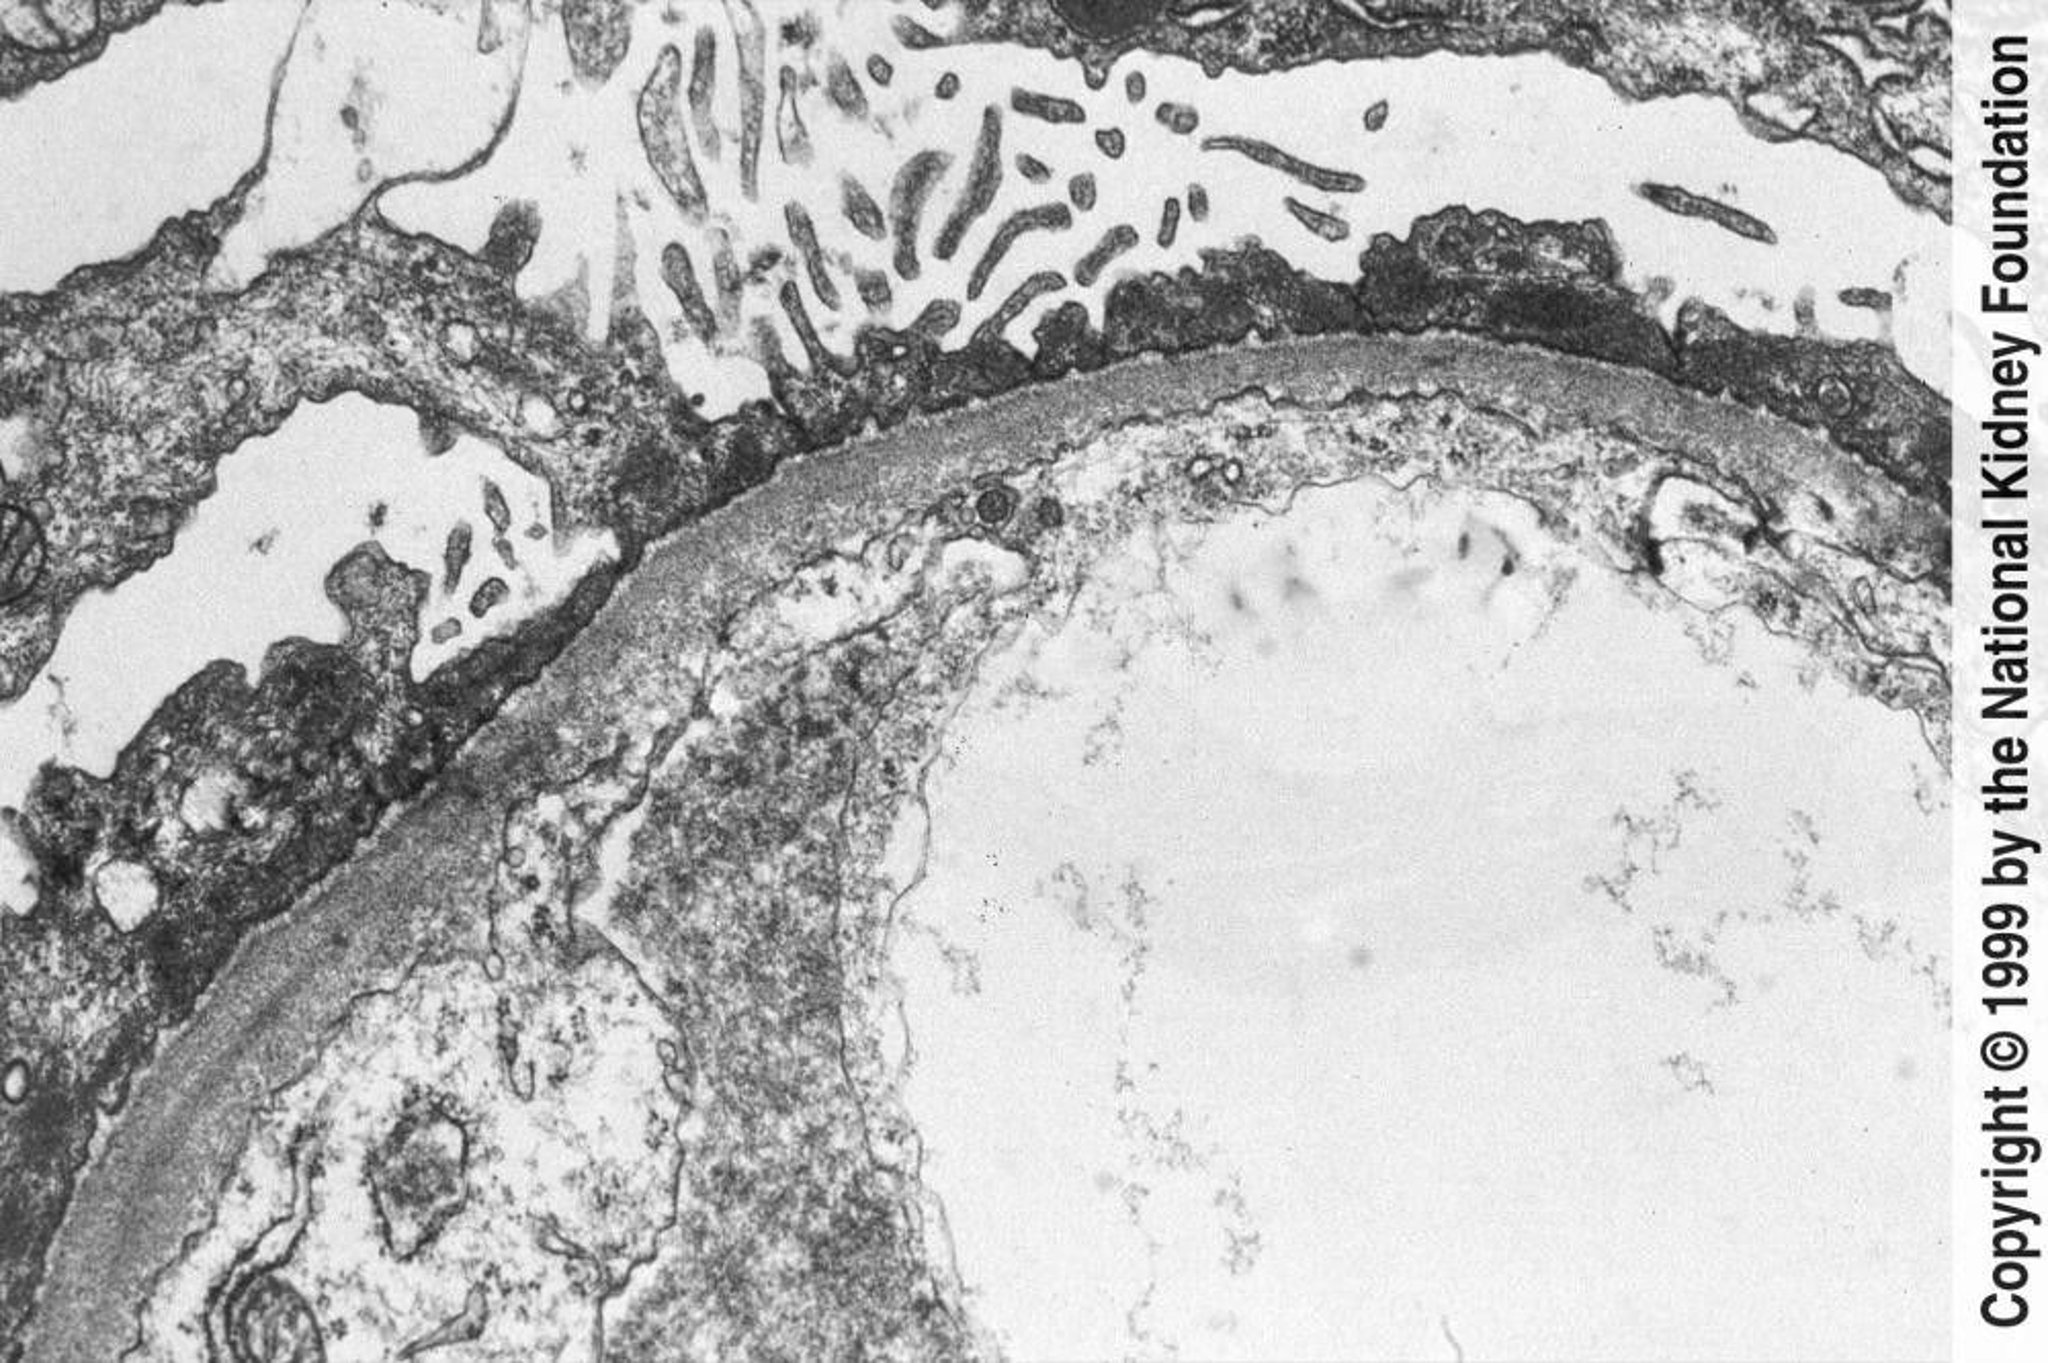

Minimal Change Disease

Diffuse effacement of foot processes can be seen on transmission electron microscopy (×800).

Image provided by Agnes Fogo, MD, and the American Journal of Kidney Diseases' Atlas of Renal Pathology (see www.ajkd.org).